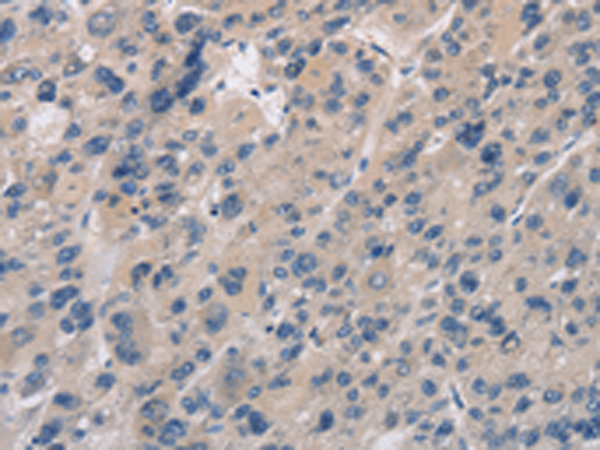

分类: 科研抗体货号: P11831别名: AME; AME1; HSD2; HSD11K; SDR9C3应用: WB,IHC反应种属: Human